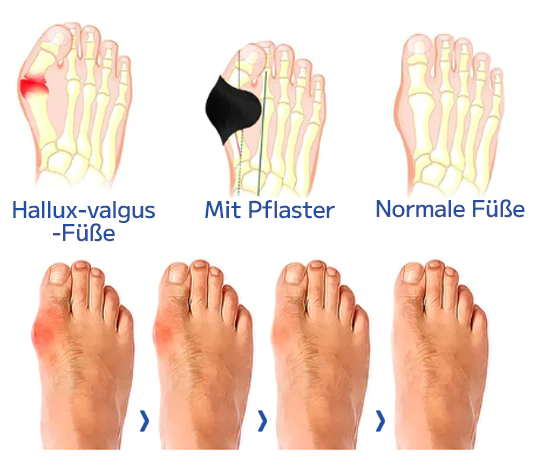

Was ist ein Ballenzeh?

Ein knöcherner Knubbel, bekannt als Hallux valgus, bildet sich an der Basis des Großzehengelenks. Dies geschieht, wenn einige der Knochen im Vorderfuß aus der Ausrichtung rutschen. Das Gelenk an der Basis des großen Zehs wird gezwungen, hervorzustehen, weil die Spitze des großen Zehs zu den kleineren Zehen gezogen wird. Über dem Hallux valgus kann es zu Schmerzen und Entzündungen kommen.

Hallux valgus oder Ballen betreffen etwa 30% der Bevölkerung. Sie entstehen durch die Fehlstellung von Metatarsal- und Phalanxknochen im Fuß, was zu einer Entzündung und Vorwölbung des Gelenks führt. Genetik, Fußverletzungen, die die Knochenstruktur verändern, und schlecht sitzende Schuhe tragen zur Bildung von Ballen bei. Diejenigen mit einer erblichen Veranlagung, flachen Bögen oder einer Vorgeschichte von Fußverletzungen sind anfälliger. Enge oder hochhackige Schuhe erhöhen das Risiko. Ballen können unbehandelt im Laufe der Zeit schlimmer werden und Unannehmlichkeiten und Schmerzen verursachen.

Ourlyard™ Bunion Relief Patch ist darauf ausgelegt, Ihren großen Zeh zu strecken und ihn an seinen richtigen Platz zurückzubringen. Es lindert nicht nur den Schmerz, die Schwellung und den Druck, die durch Ballenzehen verursacht werden, sondern hilft auch dabei, den Ballen zu reduzieren, sodass das Gelenk nicht erneut fehl ausgerichtet wird. Linderung von Schmerzen und überlappenden Zehen ohne Operation.